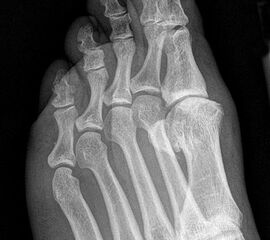

Klinisch zeigt sich stadienabhängig eine schmerzhafte Bewegungseinschränkung mit zunehmender Steifigkeit des Großzehengrundgelenkes. Vor allem die Einschränkung der Dorsalextension wird von den Patienten oft als unangenehm empfunden. Initial besteht eine bindegewebige Alteration im Gelenk, im weiteren Stadium treten Knorpeldegeneration und Begleitsynovialitis mit der Ausbildung von osteophytären Randanbauten auf. Klinische treten diese meist durch eine schmerzhafte dorsale Knochenkante in Erscheinung (Abbildung 1).

Im späten Stadium imponiert eine Gelenkblockierung durch freie Gelenkkörper. Während in den Anfangsstadien vor allem die dorsalen Anteile des Gelenks betroffen sind, betreffen die Veränderungen in den Fortgeschrittenen Stadien die gesamte Zirkumferenz einschließlich des Sesambeingleitlagers. Im Endstadium kommt es zu einer weitgehenden Ankylosierung des 1. Metatarsophalangealgelenks.

• Röntgenaufnahme des Fußes in drei Ebenen unter Belastung